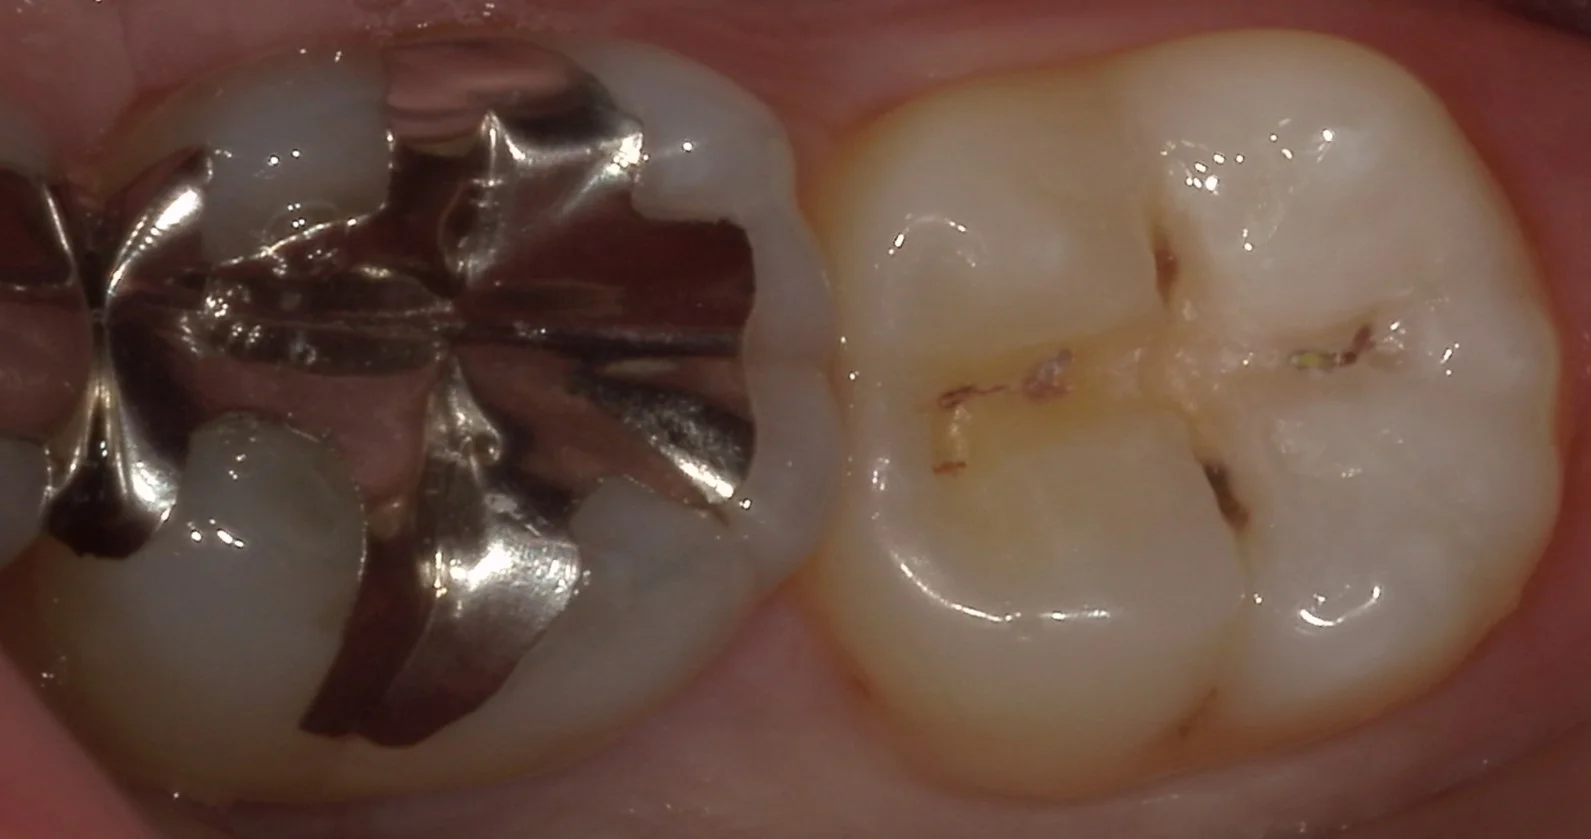

では術前の写真からです。

画像右側の写真が今回治療を行った部分になります。

もともと保険の白い詰め物で治療されていますが、透けて取り残しが見えているというのと、画像の上と下の部分に微小な漏洩が起こっており、そこから内面に大きく虫歯が進行している状態でした。

サイズで行くと非常に小さな虫歯ではありますので、保険診療でもある程度の予後は期待できるかと思われますが・・・

少しでも長く使いたいとのことでしたので、自費診療へと切り替えて治療を行うこととなりました。